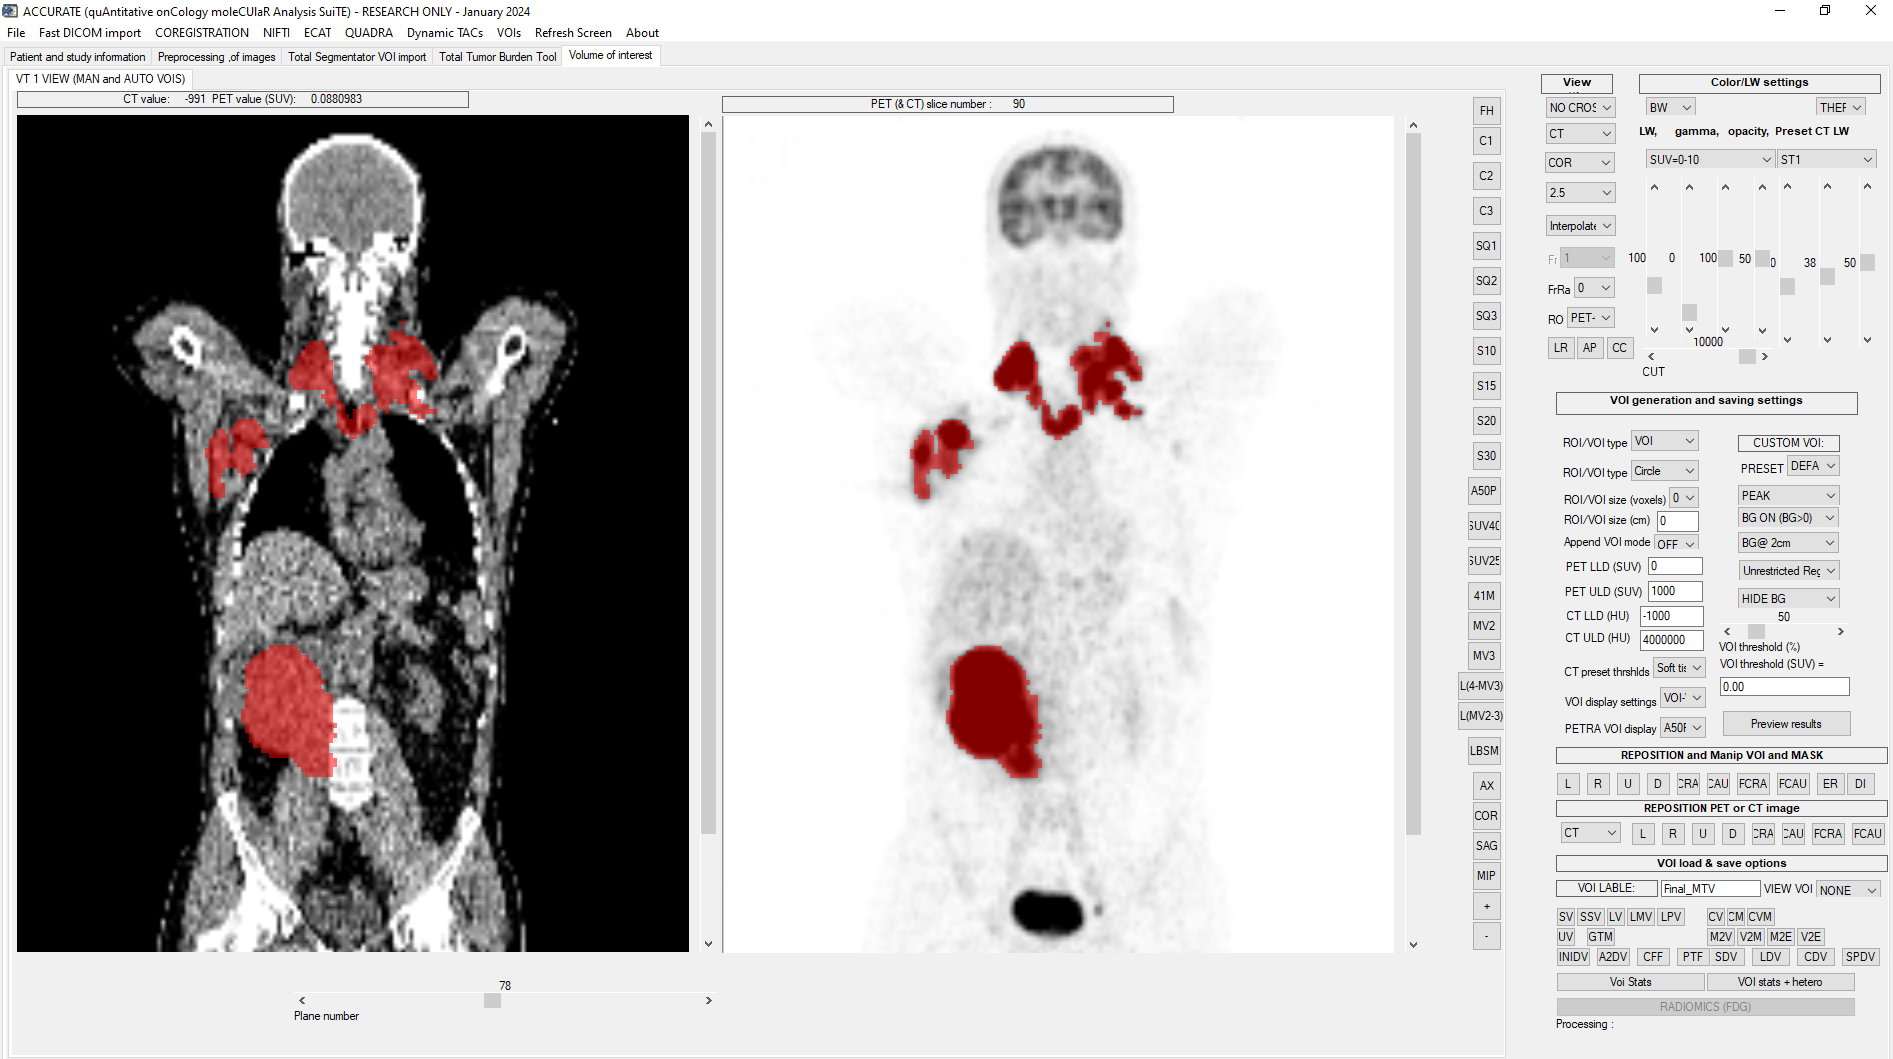

Accurate tool

ACCURATE is a software tool for quantitative analysis of (mainly) whole body PET/CT studies. The tool is developed by Ronald Boellaard (VU medical center / UMC Groningen) with input and co-development from Maqsood Yaqub (VUMC) and Floris van Velden (VUMC/LUMC). The tool is provided as a research tool only and should not be used for clinical purposes. Use of the tool is free of charge but only after consulting the primary author of the tool. The tool is continuously under development and new functionality will be added.

Analyses consists of quantification of volumes of interest (VOIs). There are different methods to obtain these VOIs:

• Manually – VOIs can be manually delineated by painting voxel per voxel

• Fixed size VOIs – A 2D or 3D VOI with a fixed size and shape can be placed

• Semi-automated –By selecting the hottest voxel as an initial starting point, a VOI will be generated automatically using a region growing algorithm. Different thresholds are available (absolute SUV thresholds, relative SUV thresholds based on SUV peak or max, with or without background correction).

The ACCURATE tool may also be used for Metabolic Tumor Volume (MTV) analyses, where the tool already makes a preselection of the total tumor burden.

Accurate for PET radiomics, MTV, SUV4